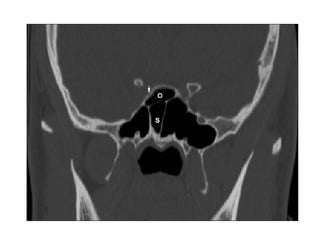

Osteomeatal unit Common DrainagePathway Of The Ant. Group of Sinuses.-Coronal scan The osteomeatal unit (OMU) includes the • uncinate process • Ethmoid infundibulum • Ethmoid Bulla • Middle Meatus • Hiatus Semilunaris Most common site of inflammatory disease